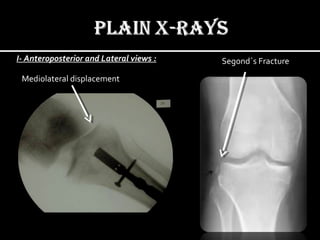

I- Anteroposterior and Lateral views :

To evaluate for fractures and/or dislocation.

Mediolateral displacement

Segond`s Fracture